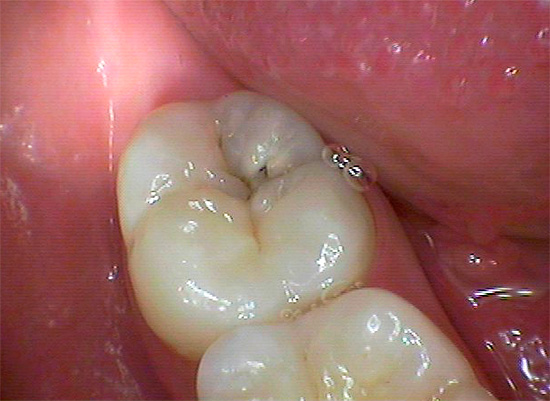

- Não há pontos e traços pretos (os últimos são característicos de cárie de fissura).

Isso é especialmente verdadeiro para fissuras, onde esses pontos às vezes podem ser muito pequenos e não se incomodam com nada, e é por isso que muitos não os percebem como um problema sério. Enquanto isso, a área da lesão sob essa mancha já pode penetrar profundamente na dentina.

Devido ao pequeno tamanho das áreas escuras na área da fissura, muitos acreditam que esses pontos podem simplesmente ser clareados ou lixados em casa, e a cárie dentária como se isso fosse curado. De fato, essa mancha é apenas um sinal de que a cárie não pode ser curada sem preenchimento.